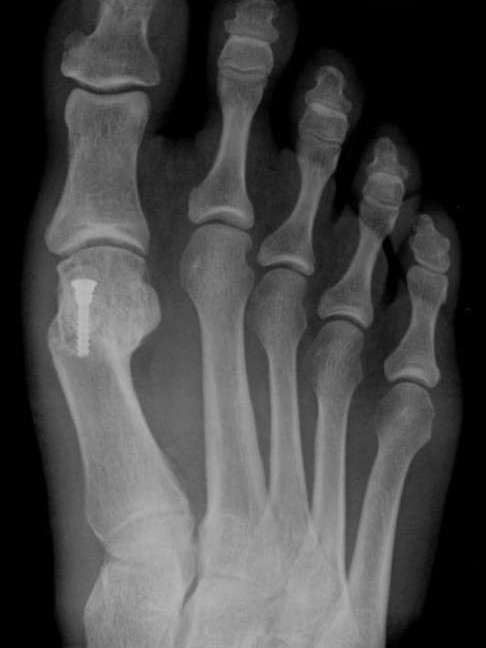

Halluks valgus ameliyatının amacı, kemiği, bağları, tendonları ve sinirleri yeniden hizalayarak, ayak başparmağının doğru konumuna geri getirilebilmesini sağlayarak ağrıyı hafifletmektir. Ameliyatlar bölgesel ya da genel anestezi ile yapılır. Halluks valgus’un farklı çeşitleri olduğu için her türe göre farklı cerrahi işlem uygulanır.

Halluks valgus cerrahisi uygulanmış hastanın röntgen filmi

Tüm ayak girişimlerinden sonra ayakta hafif de olsa ağrı, şişlik ve hareket kısıtlılığı gibi bazı yakınmaların kalacağı unutulmamalı, hiçbir ayak ameliyatı yalnızca estetik kaygılarla yapılmamalıdır. Yalnızca ağrılı bir halluks valgus için ameliyatı düşünmelidir.